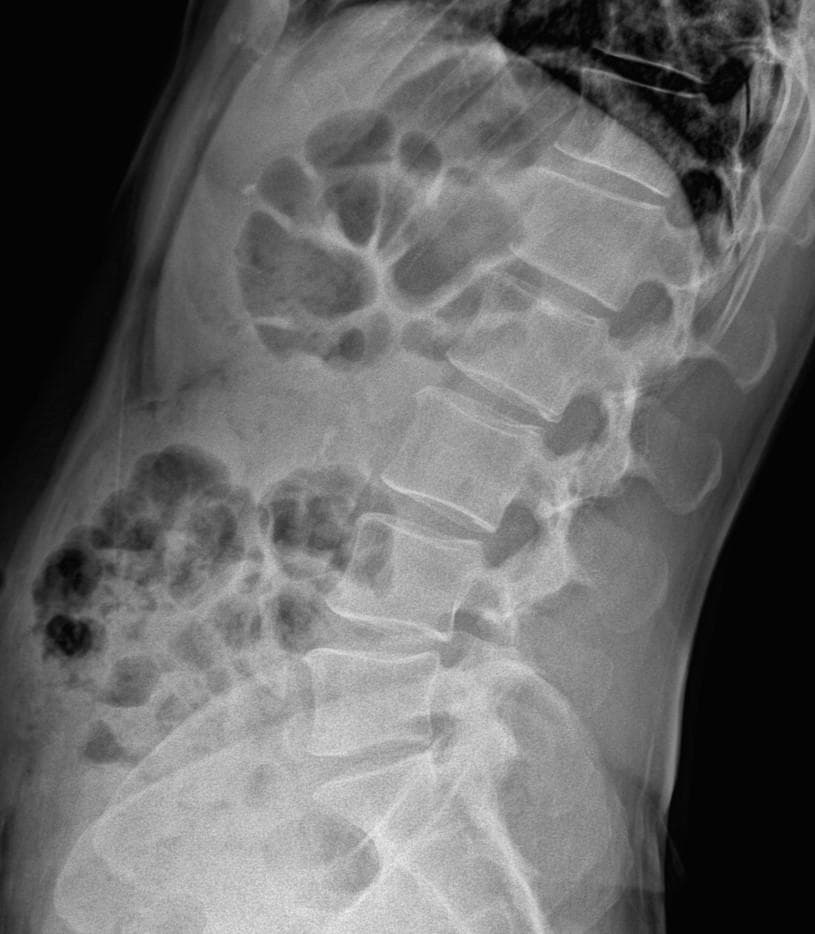

엑스레이 상에서는 요추 배열이 전반적으로 잘 유지돼 보입니다. 마나 일부 요추 간격이 좁아진 부위가 있어 보입니다. 말씀하신 것처럼 특정 동작에서 찌릿 혹은 뜨끔하거나, 최근 뻐근함이 생기는 건 디스크 초기나 근육, 인대 긴장에서도 나타날 수 있습니다.

허리의 커브가 줄어들어있다는것을 제외하고는 크게 문제가될만한 부분은없는데요 통증과불편감이 지속된다면 MRI와같은 정밀검사가 필요할수있습니다

사진상 요추 사이의 간격이 다소 좁아 보이며 간격이 좁다는 것은 퇴행성 변화를 의미하며 척추의 정렬 또한 큰 전위는 없어 보이나 허리 곡선이 정상보다는 조금 감소한 상태로 이러한 경우 근육의 긴장이나 만성적인 통증이 발생할 수 있습니다.

엑스레이 검사를 통해서는 현실적으로 뼈 위주의 평가만 가능하며 정밀하고 자세하게 평가를 내리는 것은 어렵습니다. 올리신 엑스레이 사진들에는 특별히 문제가 있다고 볼만한 소견이 크게 있어보이거나 하지는 않습니다.

우선 현재로썬 척추와 척추 사이인 디스크 공간이 좁지는 않아보이지만 다소 요추의 커브가 감소되어 있어 보입니다.